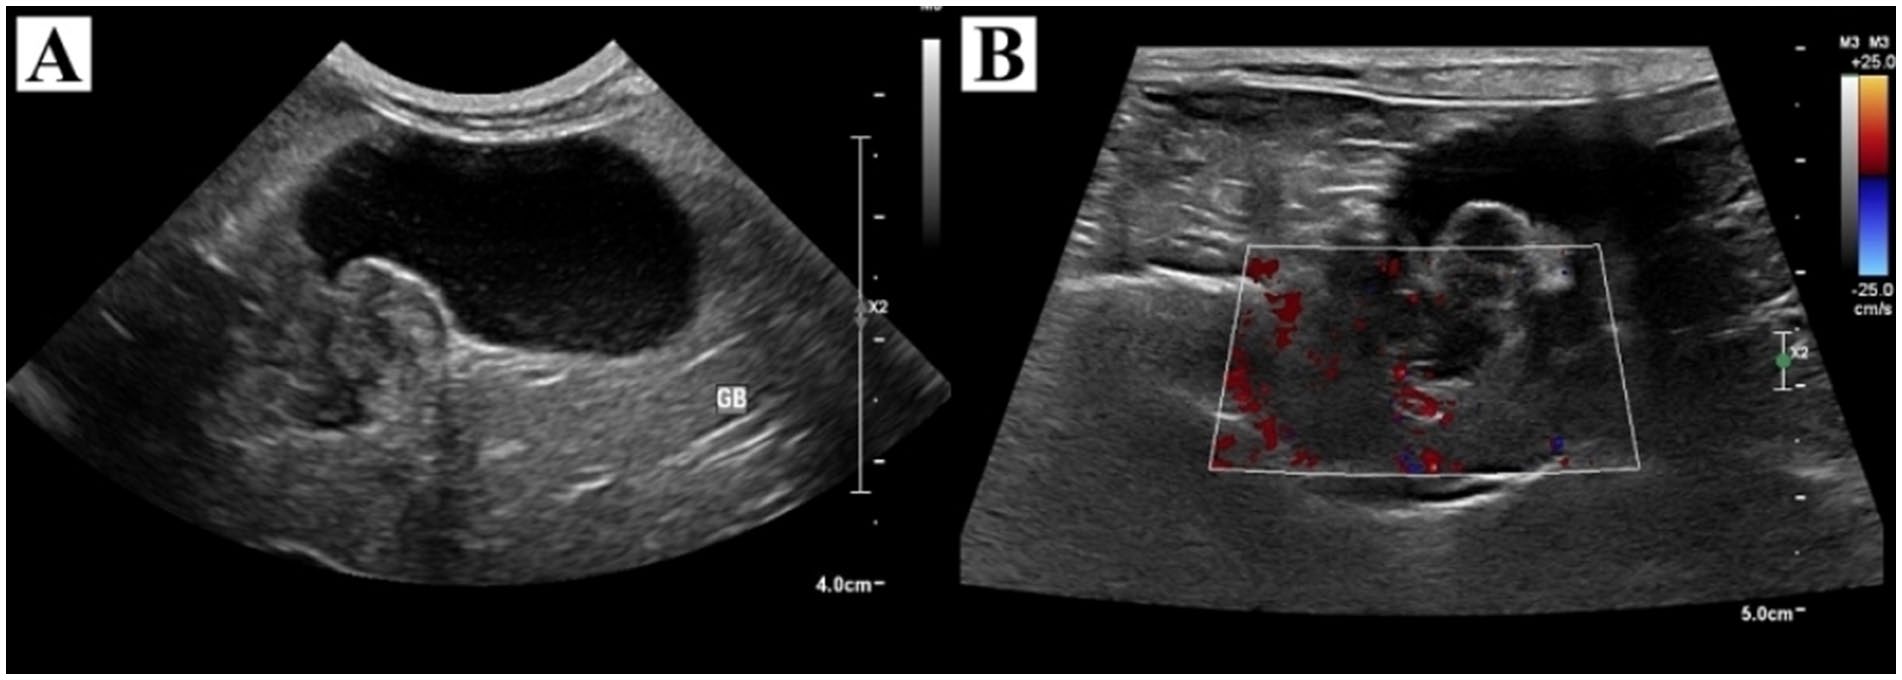

胸腹部X线片未见异常。腹部超声可见胆囊明显扩张,胆囊颈部呈1.7 × 1.5 cm、广基、迂曲,并见一内部回声不均的团块(图1)。彩色多普勒成像显示团块内无明显血流信号。胆总管轻度扩张。腹部超声未见转移征象。因主人经济限制,术前未行CT检查。

图1. (A) 胆囊明显扩张,颈部可见回声不均的团块,胆囊壁无增厚。(B) 彩色多普勒成像显示团块内无明显血流信号。

基于影像表现,主要考虑胆囊肿瘤(如神经内分泌癌、腺癌、平滑肌瘤、腺瘤及淋巴瘤)。然而,由于超声影像特征重叠,亦需排除由胆栓或非重力依赖性胆汁淤积所致的部分肝外胆道梗阻。